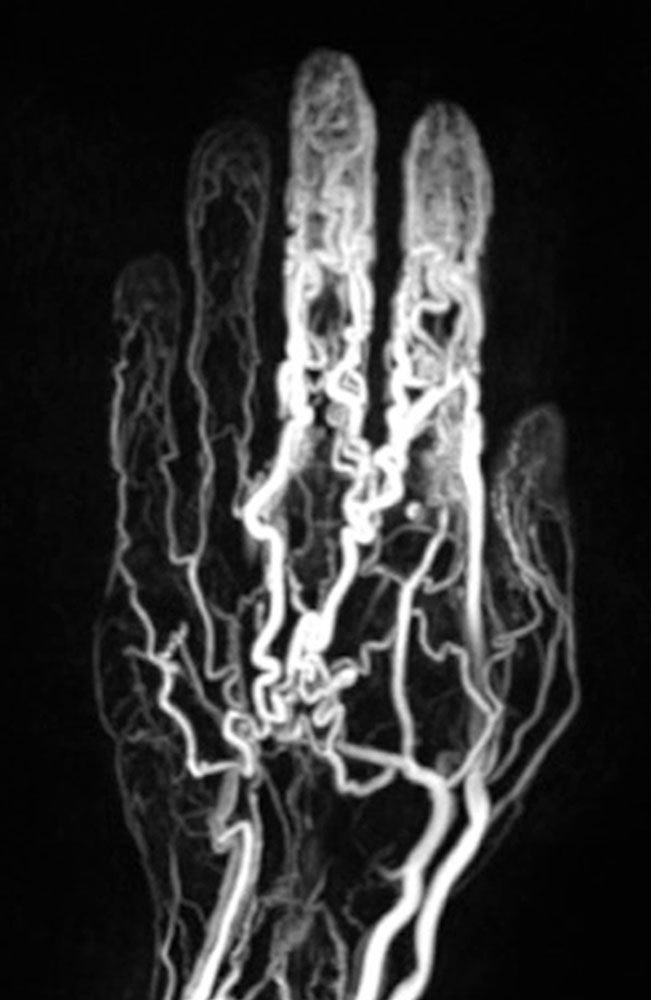

In addition, cross-sectional imaging using computed tomography (CT) or magnetic resonance imaging (MRI) is required to confirm the diagnosis, localization and involvement of organs. CT with contrast agent administration plays a lesser role in this context: it can easily detect bony involvement of the arteriovenous malformation, but spread to soft tissues is better visualized by MRI. The hemodynamics of the lesion can also be visualized by dynamic, contrast-enhanced MR angiography. In MRI, so-called flow voids are present in sequences without contrast medium because of the rapid blood flow. The dilated arteries supplying the nidus ("feeder arteries") usually follow a tortuous course. Depending on the angioarchitecture, single dominant dilated veins or several more net-like dilated veins can be delineated as the outflow of the lesion. The surrounding tissue may show edematous or fibrous-fatty changes. Involved bony structures may exhibit lytic changes or hyperplasia.

In most cases, catheter angiography is only performed as part of a minimally invasive treatment. The arteries supplying the nidus are often twisted, dilated and sometimes aneurysmally dilated. As a result of the arteriovenous shunt connections, there is immediate, early contrast filling of the dilated veins.